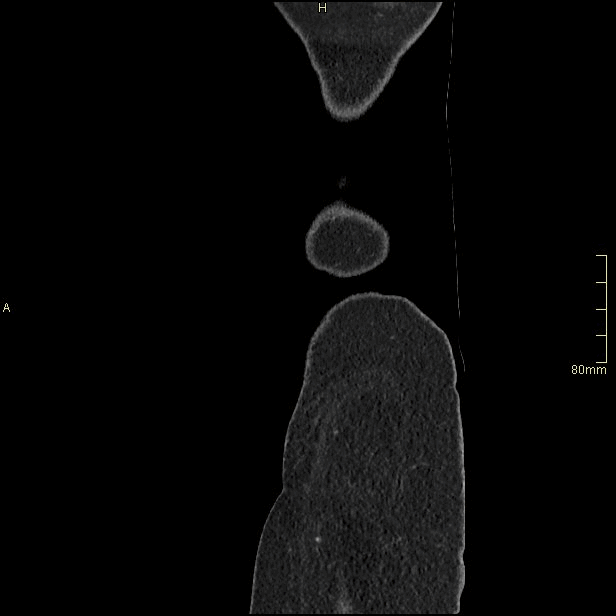

For patients over the age of 40, a non contrast KUB, and seperate nephrogenic and excretory (delayed) phases will be performed. For all patients under the age of 40, a non contrast KUB and a COMBINED dual nephrogenic/excretory phase will be performed. Image examples of this can be seen below.

Under 40 Years of Age

CT Urogram- Nephrogenic + Excretory Phase (Sagittal)